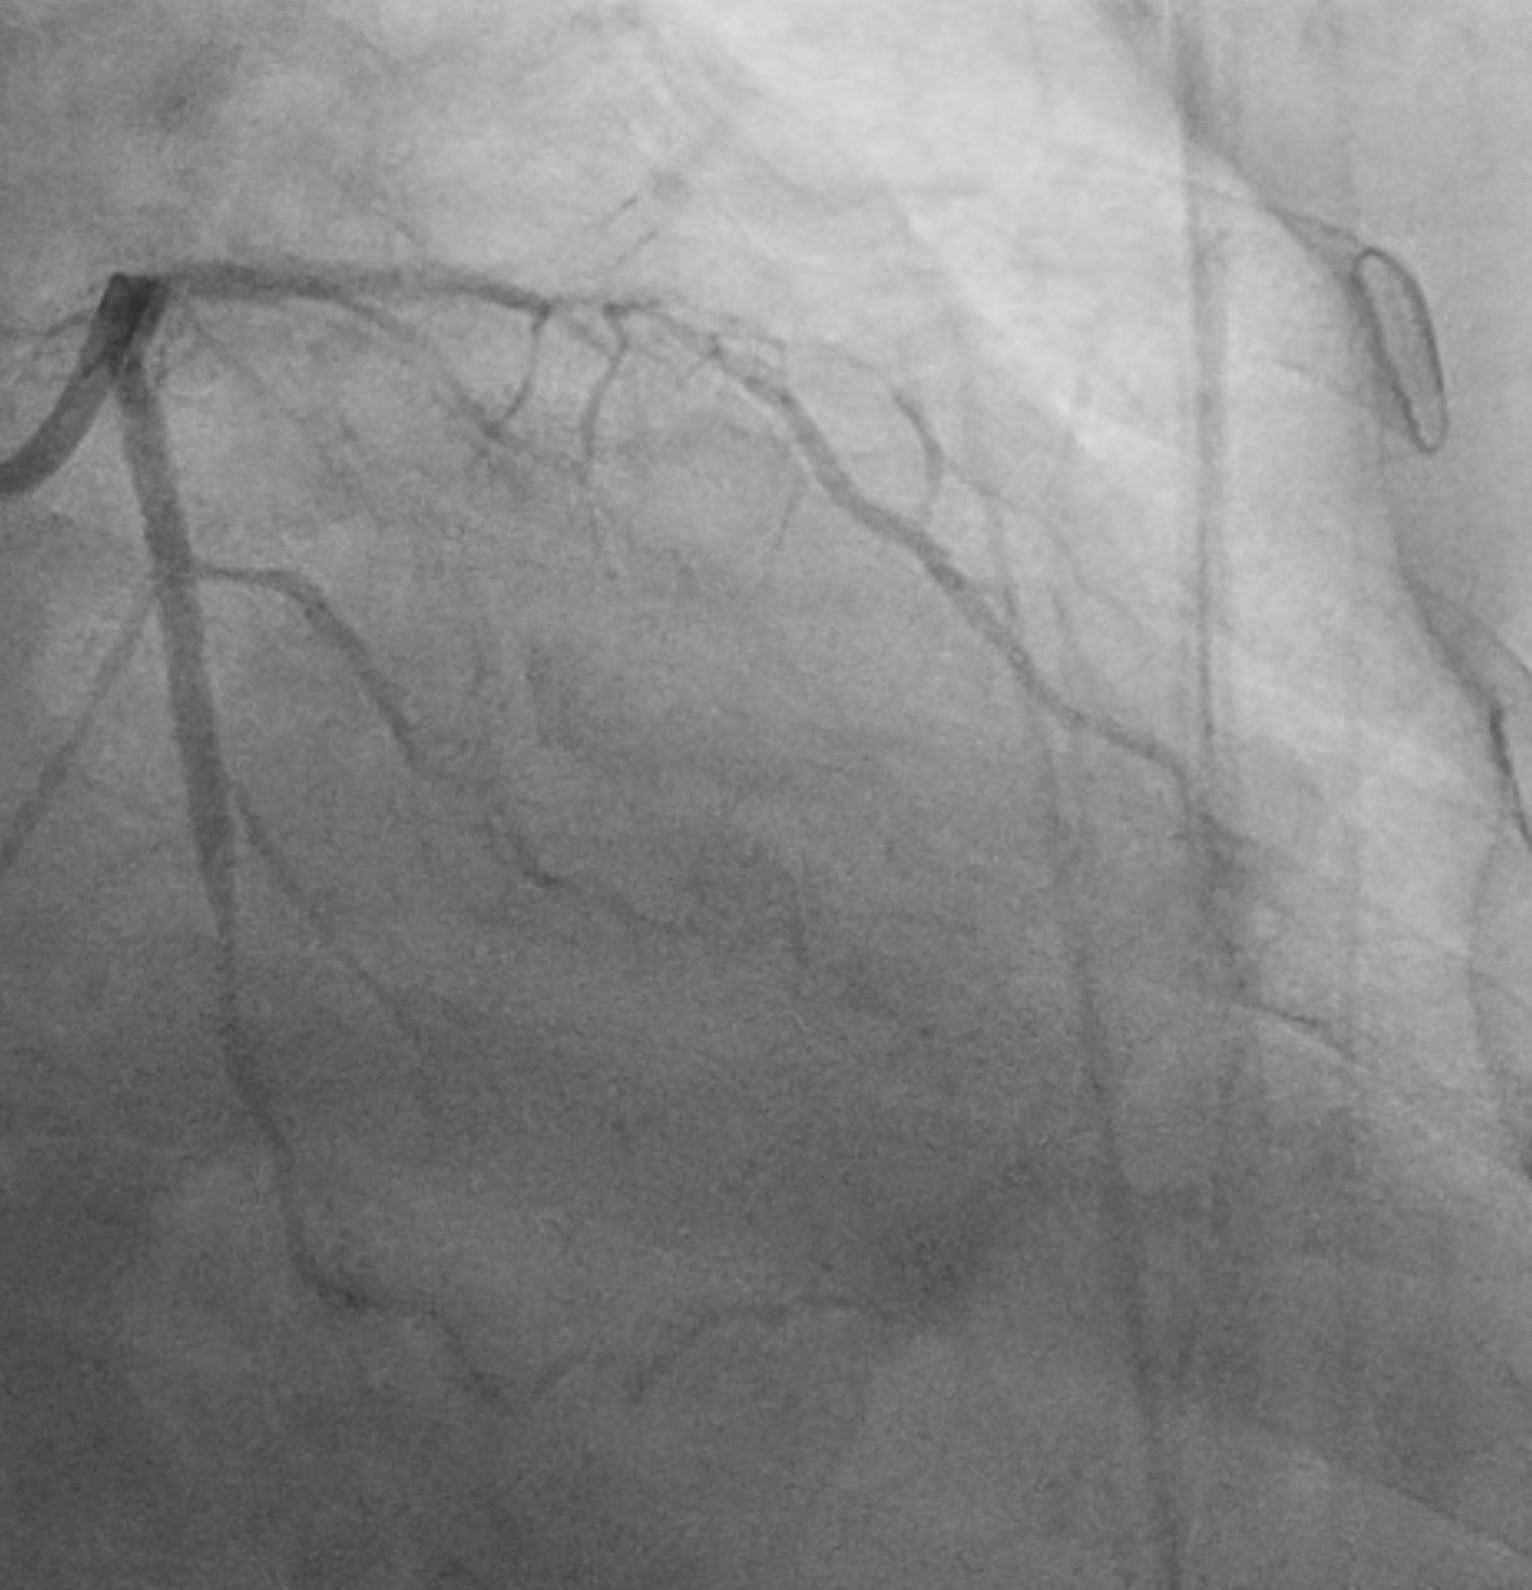

Initial angiography at our facility revealed patent stent at osteal to mid RCA.Left coronary angiography showed patent stent at proximal to distal LCx anddiffuse, severe and heavy calcified stenosis at proximal to distal LAD.

PCIof the LAD was performed via femoral access using a BL 3.5/7F guiding catheter.A Runthrough Hypercoat wire was advanced distally without difficulty. The OCTcatheter failed to cross the lesion, and a 2.5 ¡¿ 15 mm scoring balloon couldnot pass the mid LAD. A microcatheter was inserted, and the wire was exchangedfor a Rotawire. Rotational atherectomy was performed using a 1.25 mm burr withshort, gentle pecking runs at 180,000 rpm, followed by upsizing to a 1.5 mmburr for three runs at 200,000 (2 times) and 160,000 rpm. The burr advancedsmoothly with improved tactile feedback, suggesting successful plaquemodification. The wire was exchanged back to a Runthrough, and OCT (DragonflyOPTIS) imaging showed an MLA of 1.43 mm©÷ at mid LAD with severe 360¡Æ calcification(0.9 mm thick, 41 mm long) and a napkin-ring pattern. A 2.5 ¡¿ 15 mm cuttingballoon was used with multiple 14–18 atm inflations, producing a visible¡°crack¡± in the calcified cap. Angiography and repeat OCT confirmed the calciumfracture. A 3.0 ¡¿ 46 mm DES was deployed from the ostial to distal LAD at 14atm and post-dilated with a 3.5 mm NC balloon proximally. Final angiographyshowed TIMI 3 flow. OCT demonstrated excellent stent expansion (MSA 7.78 mm©÷proximal, 3.28 mm©÷ distal) without dissection and with 107% stent expansion.